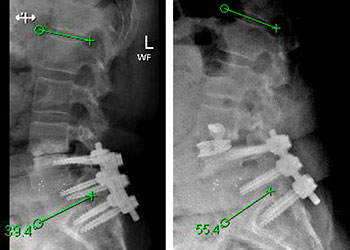

Fig 1. Head CT scan showing large right-sided, parieto-occipital intra-cerebral hemorrhage (ICH) and small occipital and temporal subdural hemorrhage (SDH) with right to left midline shift (red arrow).

A head CT revealed a large posterior-parietal intracerebral bleed, an acute subdural clot, and right to left midline shift (Fig 1). Following the review of a head CTA, the patient was diagnosed with a ruptured brain arteriovenous malformation (AVM). Urgent treatment was indicated for this acute intracerebral hemorrhage (ICH) with significant mass effect and the risk of catastrophic rebleeding of the AVM.